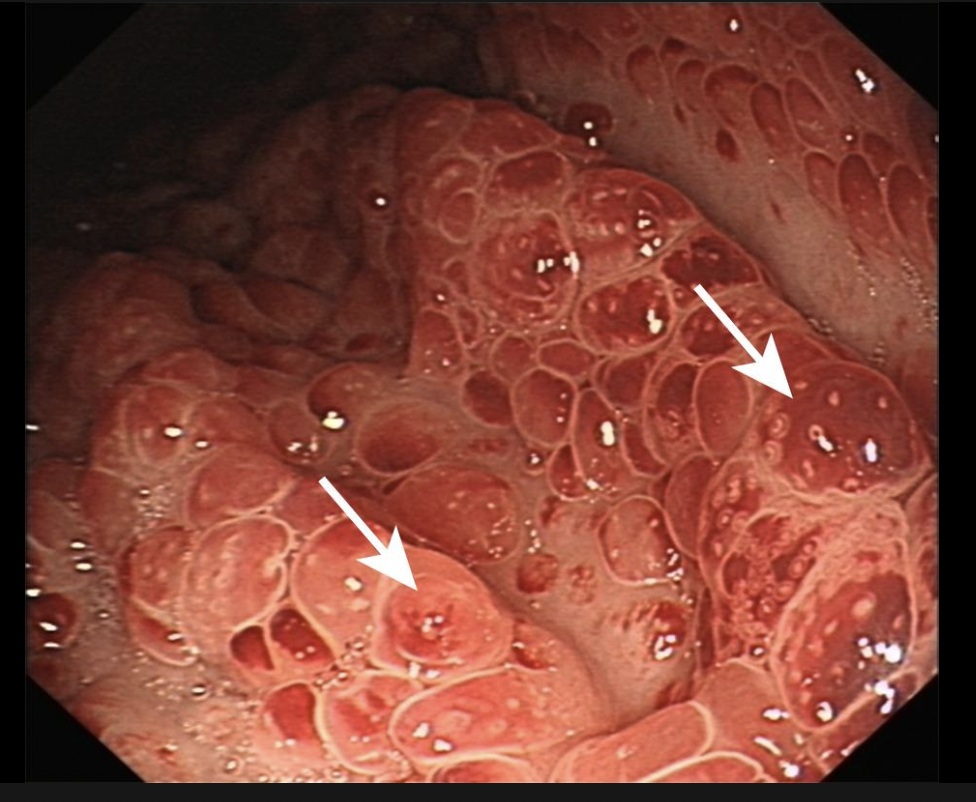

many hamartomatous polyps

Cronkit-canada syndrome

(not genetically inheritied)